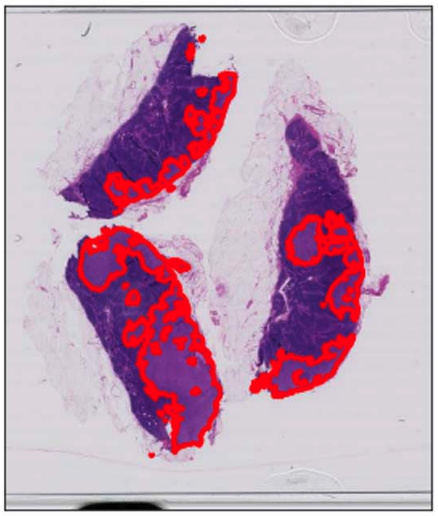

Tools in Digital Pathology

tumor

non tumor

Can we refine these automatically?

false positives

false negatives

• Training on a single slide

necrotic tumor

viable tumor

non-tumor

Manual coarse annotation

Computational refinement

Ground truth